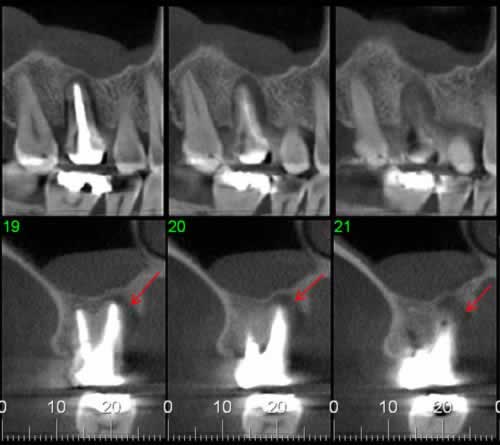

Caso 5: Dente retido

Dente 47 e 48 retidos, em posição mésio horizontal, sobrepostos com raízes superpostas ao canal mandibular. Ao exame tomográfico identifica-se o canal passando rechaçado entre os ápices do 48 e a cortical vestibular e passando entre as duas raízes mesiais do dente 47.